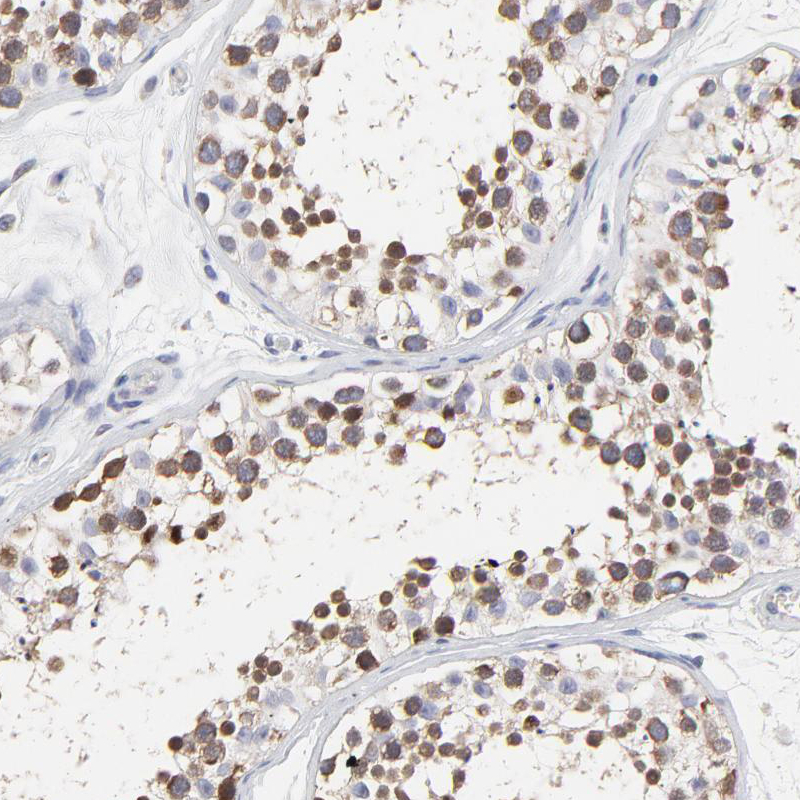

Immunohistochemistry analysis in human testis and kidney tissues using HPA002647 antibody. Corresponding NCAPH RNA-seq data are presented for the same tissues.